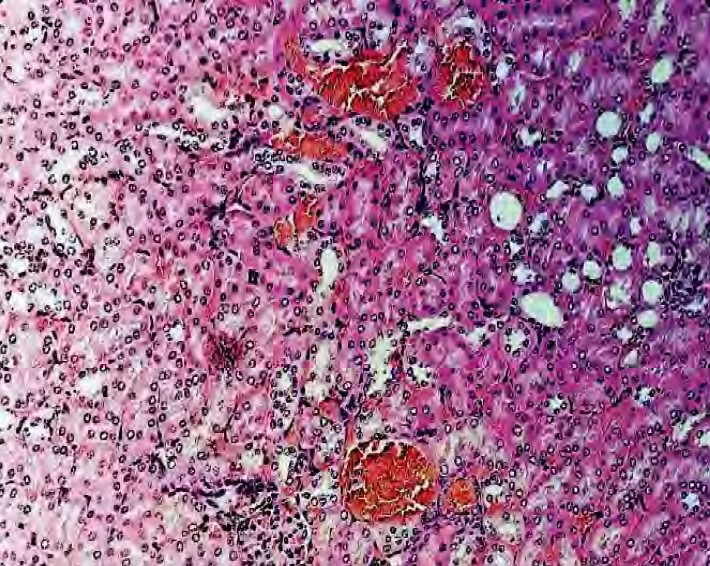

Fig. 3. Rabbit liver when infected with bacteria P. aeruginosa. Hematoxylin and eo-sin. Magnification: 10 × 20, H604 Trinocular Unico, USA

Source: made by the authors